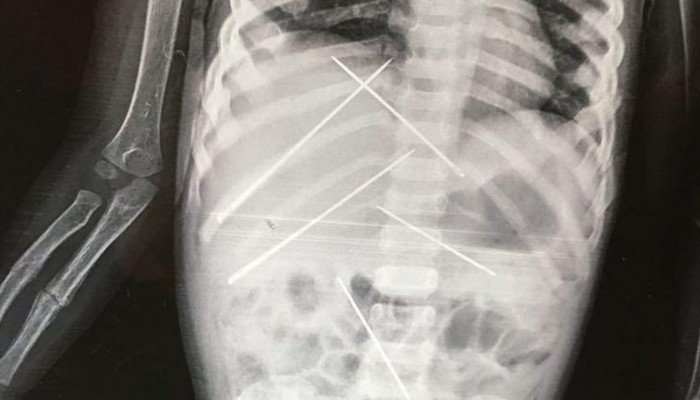

Όπως αποκαλύφθηκε η μικρούλα είχε στο κορμάκι της 7 βελόνες, οι οποίες είχαν χρησιμοποιηθεί πάνω της σε… τελετές μαύρης μαγείας.

Οι γιατροί έκαναν ακτινογραφίες στο σώμα της μικρής, όταν έκπληκτοι διαπίστωσαν πως μέσα στο σώμα της βρίσκονταν 7 μεγάλες βελόνες, ενώ διαπίστωσαν πως το ένα της χέρι ήταν σπασμένο.

Το κοριτσάκι υποβλήθηκε σε εγχείρηση και της αφαιρέθηκαν οι βελόνες. Οι βελόνες βρίσκονταν μέσα στο κορμάκι της για τουλάχιστον 15-20 ημέρες.